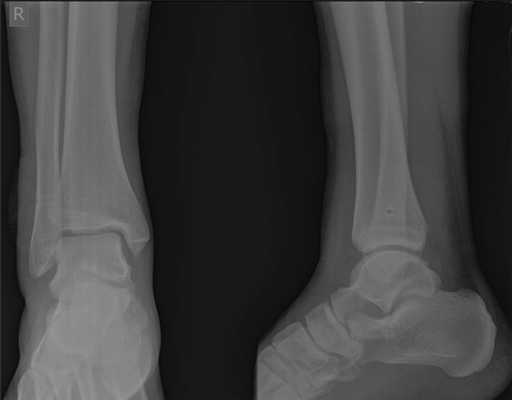

Очень важно чтобы при первичном обращении в травмпункт, пациентам с повреждением связочного аппарата голеностопного сустава производились полноценные рентгенограммы, стоя с нагрузкой весом тела, косая проекция с внутренней ротацией голени 15 градусов, а при необходимости, и стресс-рентгенограммы.

При детальном изучении снимков определяется увеличение межберцовой щели до 7,5 мм, уменьшения зоны перекрытия большеберцовой и малоберцовой костей до 5 мм, отсутствие на стороне поражения перекрытия тени таранной кости и малоберцовой кости.

На рентгенограмме костей правого и левого голеностопных суставов в прямой проекциии, снимки стоя - справа определяются признаки повреждения дистального межберцового синдесмоза - степень взаимного перекрытия берцовых костей 5мм (в норме больше 6мм) увеличенное большеберцовое - малоберцовое пространство - 7.5мм (в норме до 6мм).

При выполнении стресс рентгенограмм определяется выраженная латеральная нестабильность голеностопного сустава.